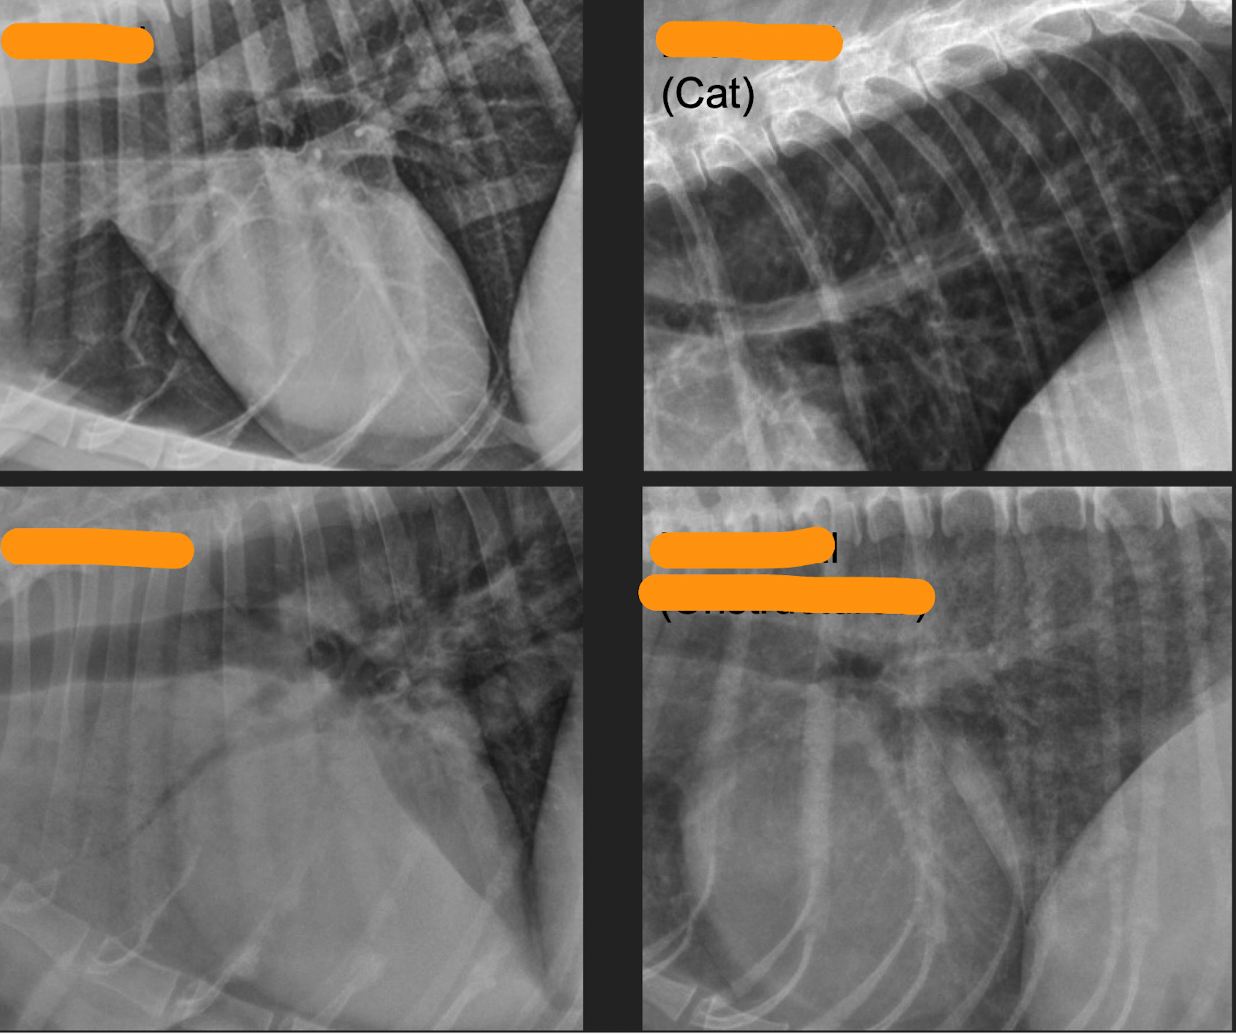

Q

compare nodules

A